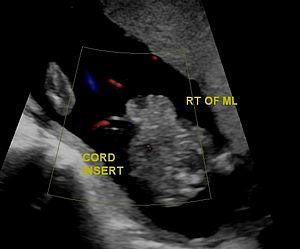

Gastrochisis in ultrasound: defect is right to midline

The cause is typically unknown.[3][1] Rates are higher in babies born to mothers who smoke, drink alcohol, or are younger than 20 years old.[3][1] Ultrasounds during pregnancy may make the diagnosis.[1] Otherwise diagnosis occurs at birth.[1] It differs from omphalocele in that there is no covering membrane over the intestines.[3]

There are no signs during pregnancy. About sixty percent of infants with gastroschisis are born prematurely.[5] At birth, the baby will have a relatively small (<4 cm) hole in the abdominal wall, usually just to the right of the belly button.[6] Some of the intestines are usually outside the body, passing through this opening. In rare circumstances, the liver and stomach may also come through the abdominal wall.[7] After birth these organs are directly exposed to air.[5]

In the developed world, around 90% of cases are identified during normal ultrasound screens, usually in the second trimester.[17]

Distinguished from other ventral body wall defects such as omphalocele, there is no overlying sac or peritoneum, and the defect is usually much smaller in gastroschisis.[10]